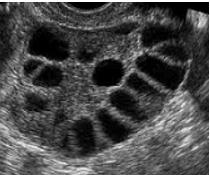

- Én eller begge æggestokke skal være med mange små ægblærer (follikler).

Unge kvinder under 18 år / tidligst 8 år efter menarche (den første menstruation) vil naturligt have mange ægblærer ved ultralyd, så for at undgå overdiagnostik anbefales ikke at udrede for PMOS/ PCOS før start 20’erne